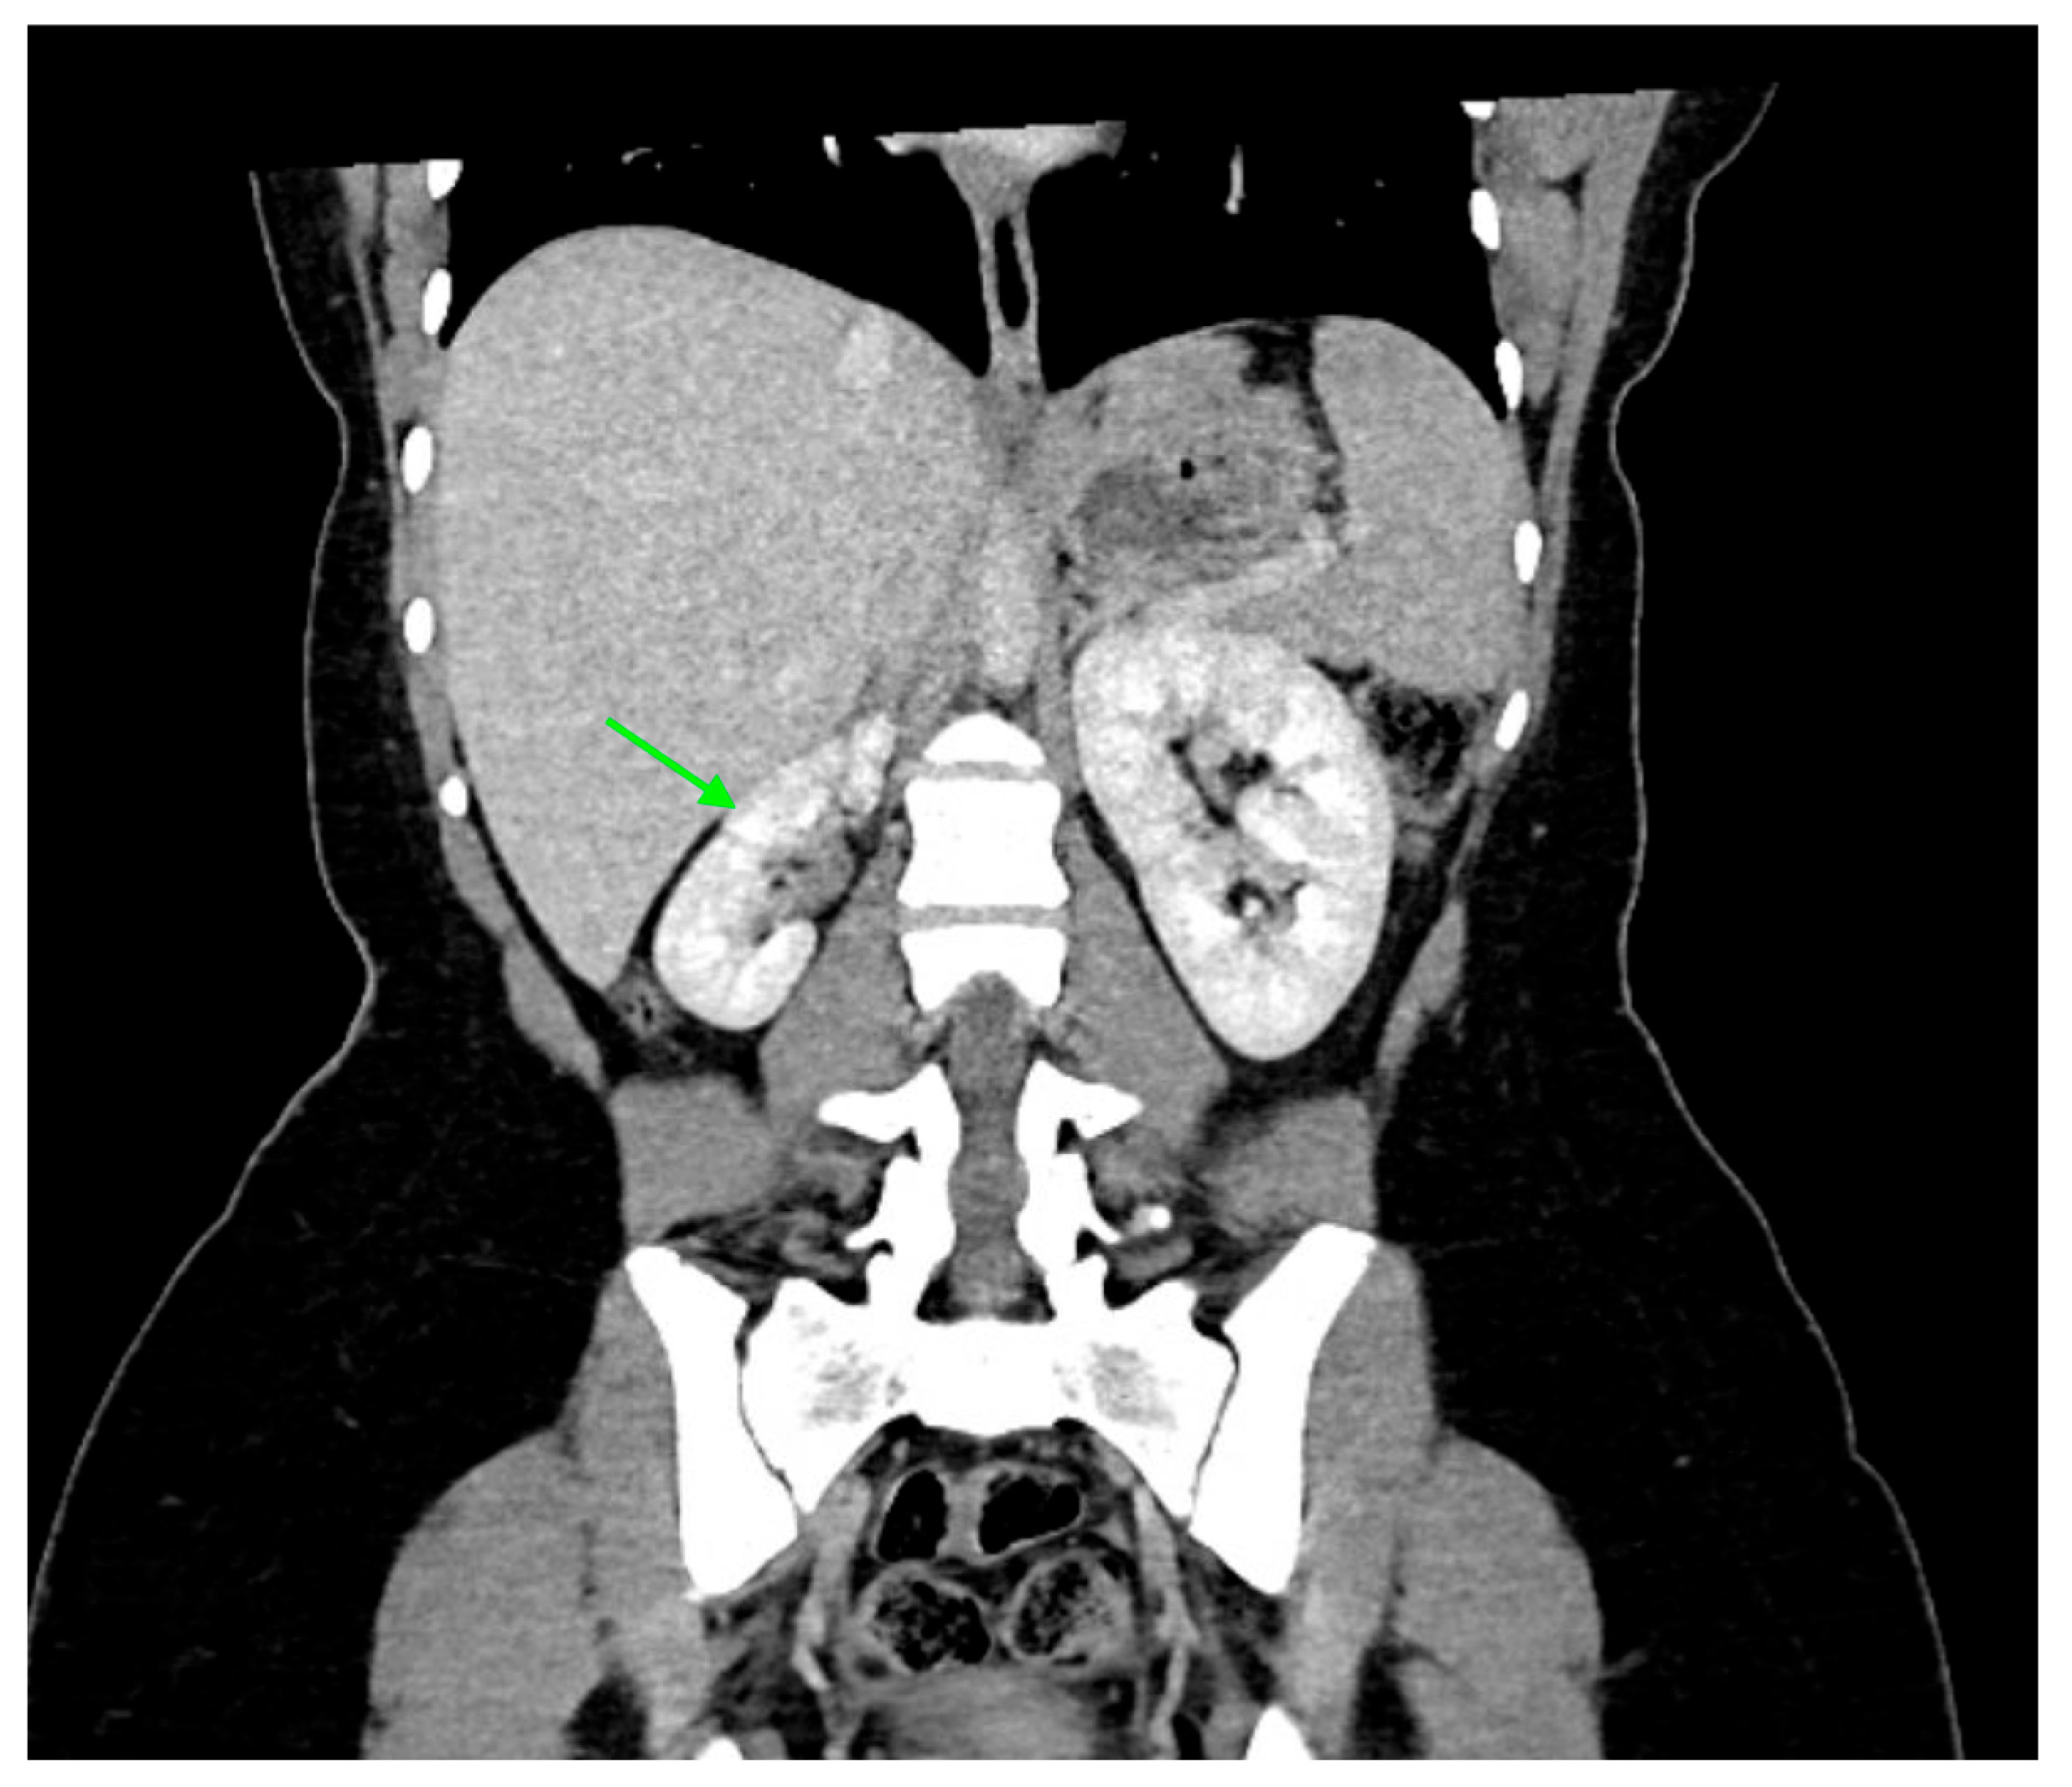

5. Computed Tomography (CT)

5.1. Technique

5.2. Application

23. Urinary Tract Tumors